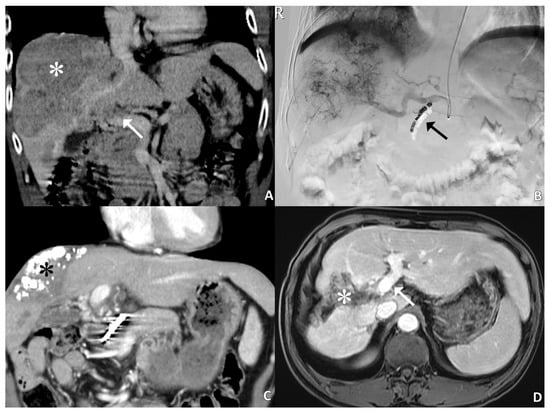

2.2. Temporary Infusion System

- Liang, H.L.; Huang, J.S.; Lin, Y.H.; Lai, K.H.; Yang, C.F.; Pan, H.B. Hepatic arterial infusion chemotherapy for advanced hepatocellular carcinoma by placing a temporary catheter via the subclavian route. Acta Radiol. 2007, 48, 734–740. [Google Scholar] [CrossRef] [PubMed]

- Tsai, W.L.; Lai, K.H.; Liang, H.L.; Hsu, P.I.; Chan, H.H.; Chen, W.C. Hepatic arterial infusion chemotherapy for patients with huge unresectable hepatocellular carcinoma. PLoS ONE 2014, 9, e92784. [Google Scholar] [CrossRef] [PubMed]